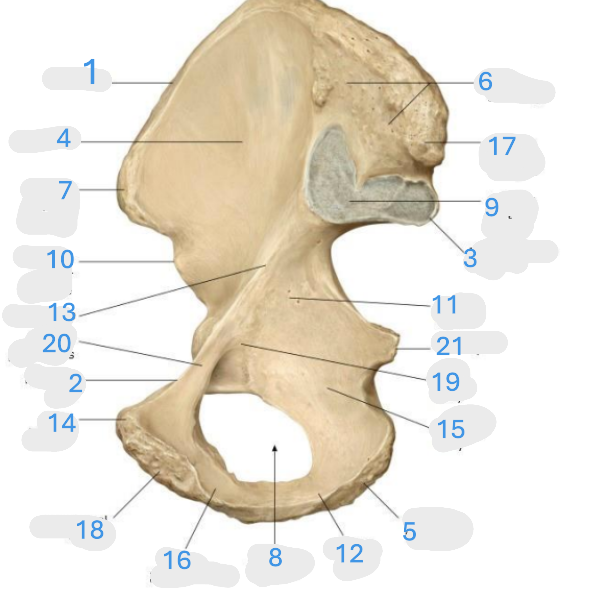

Where is the iliac crest

1

Where is the pectineal line

2

Where is the posterior iliac spine

3

Where is the iliac fossa

4

Where is the ischial tuberosity

5

Where is the iliac tuberosity

6

Where is the anterior superior iliac spine

7

Where is the obturator foramen

8

Where is the auricular surface of the ilium

9

Where is the anterior inferior iliac spine

10

Where is the ilium body

11

Where is the ischial ramus

12

Where is the arcuate line

13

Where is the pubic tubercle

14

Where is the ischium body

15

Where is the inferior pubic ramus

16

Posterior superior iliac spine

17

Where is the symphyseal surface

18

Where is the pubis body

19

Where is the superior pubic ramus

20

Where is the ischium body

21